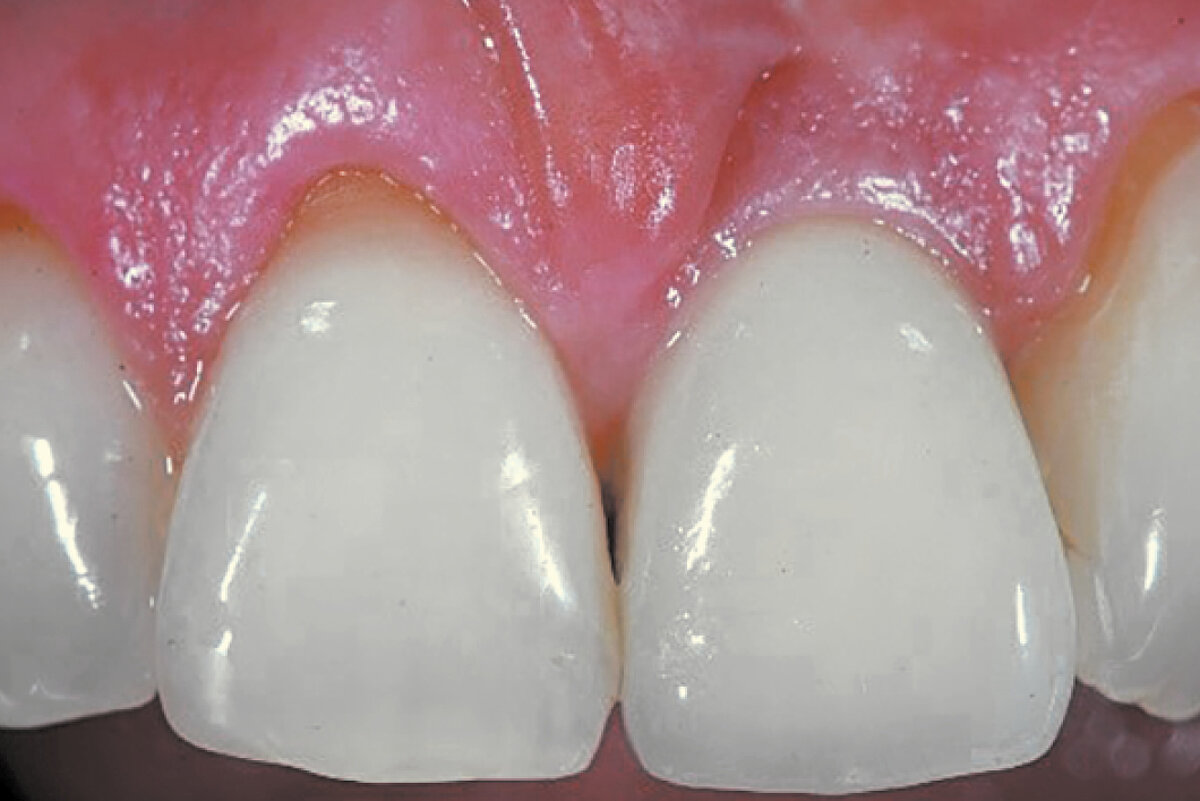

Geistlich Bio-Oss® Collagen and Geistlich Mucograft® Seal preserve the ridge for optimal implant placement 5 months post-op. At the central incisor, the buccal soft-tissue thickness is optimised with a connective tissue graft.

Soft and hard tissues are well preserved without any scarring on the buccal or occlusal aspect.